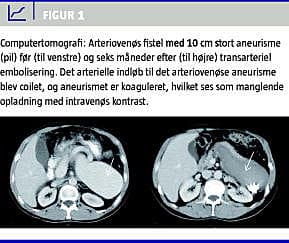

Treogtyve år efter splenektomi efter trafiktraume med miltlæsion blev en 50-årig mand indlagt med akut øvre gastrointestinal blødning. Patienten var igennem de seneste år blevet behandlet for tiltagende astma bronchiale. Med transtorakal ekkokardiografi fire år før indlæggelsen påvistes dilateret venstre ventrikel (slutdiastolisk diameter 60 mm) med normal venstre ventrikel-uddrivningsfraktion. I månederne op til indlæggelsen havde patienten bemærket en udfyldning i epigastriet. Ved indlæggelsen påvistes ved gastroskopi øsofagusvaricer. Ved computertomografi af thorax og abdomen påvistes en fistel med et 10 cm stort aneurisme mellem arteria og vena lienalis, dilaterede hepatiske vener, ascites, korektasi og lungestase (Figur 1 ). Fornyet transtorakal ekkokardiografi påviste svær trikuspidalinsufficiens med returgradient over trikuspidalklappen på 57 mm Hg og en betydeligt dilateret vena cava inferior, der målte 35-40 mm i tværmål. Patienten var nu i New York Heart Association (NYHA)-klasse IV. Der blev foretaget perkutan transarteriel coiling af arteria lienalis på Karkirurgisk Afdeling på Rigshospitalet, hvorved AV-fistlen lukkedes, og patientens akutte kardielle belastning aftog. Ved opfølgende computertomografi et år senere var fistlen fortsat lukket. Patienten var i antikongestiv behandling med betablokker og angiotensinkonverterende enzym (ACE)-hæmmer, hvorunder venstre ventrikels uddrivningsfraktion var øget fra 40% (efter et år) til 52% (efter halvandet år) bedømt ved ekkokardiografi og ved myokardieskintigrafi. Den slutdiastoliske diameter var over samme periode normaliseret fra 63 til 52 mm. Klinisk var patienten ved seneste opfølgning i NYHA-klasse I og havde genoptaget sit arbejde som murer på fuld tid.